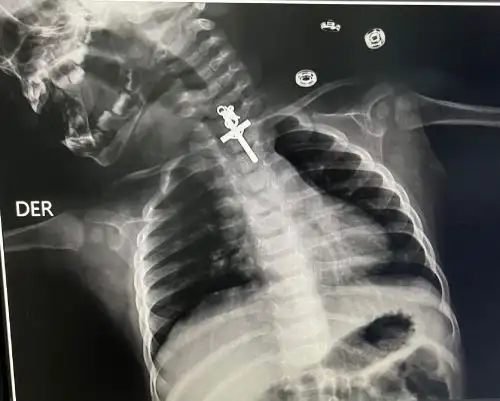

Allí fue sometida a un examen de tórax, lo que reveló que la menor tenía un crucifijo de metal alojado en el esófago.

De inmediato, los médicos del servicio de gastroenterología le

realizaron una endoscopía terapéutica, logrando extraer con éxito el objeto extraño. Luego pasó a recuperación, donde fue monitoreada de manera constante por el personal de EsSalud.

“Le realizamos una endoscopia terapéutica, pues la bebita se tragó un crucifijo y tuvimos que esperar seis horas para que el estómago se vaciara ya que había tomado su leche. Luego de eso, se procedió con la compleja intervención y todo salió muy bien, gracias a los grandes profesionales con que contamos”, indicó el gastroenterólogo Luis Alberto Esteves Cabanillas.